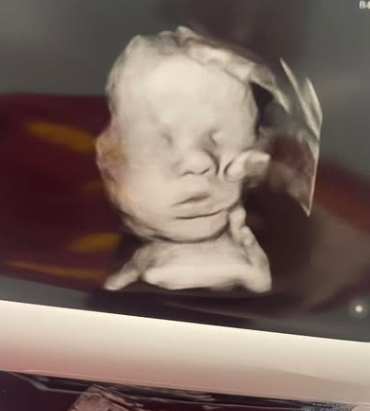

Mutter sieht „Hand Gottes“, die Kopf ihres Babys im Ultraschall hält

Symbolfoto: Shutterstock In dem, was als modernes Wunder bezeichnet wird, sagt eine Mutter aus dem US-Bundesstaat Kentucky, ihr ungeborenes Baby sei von der „Hand Gottes“ berührt worden – und sie hat den Ultraschall, um es zu beweisen. Im April 2022…